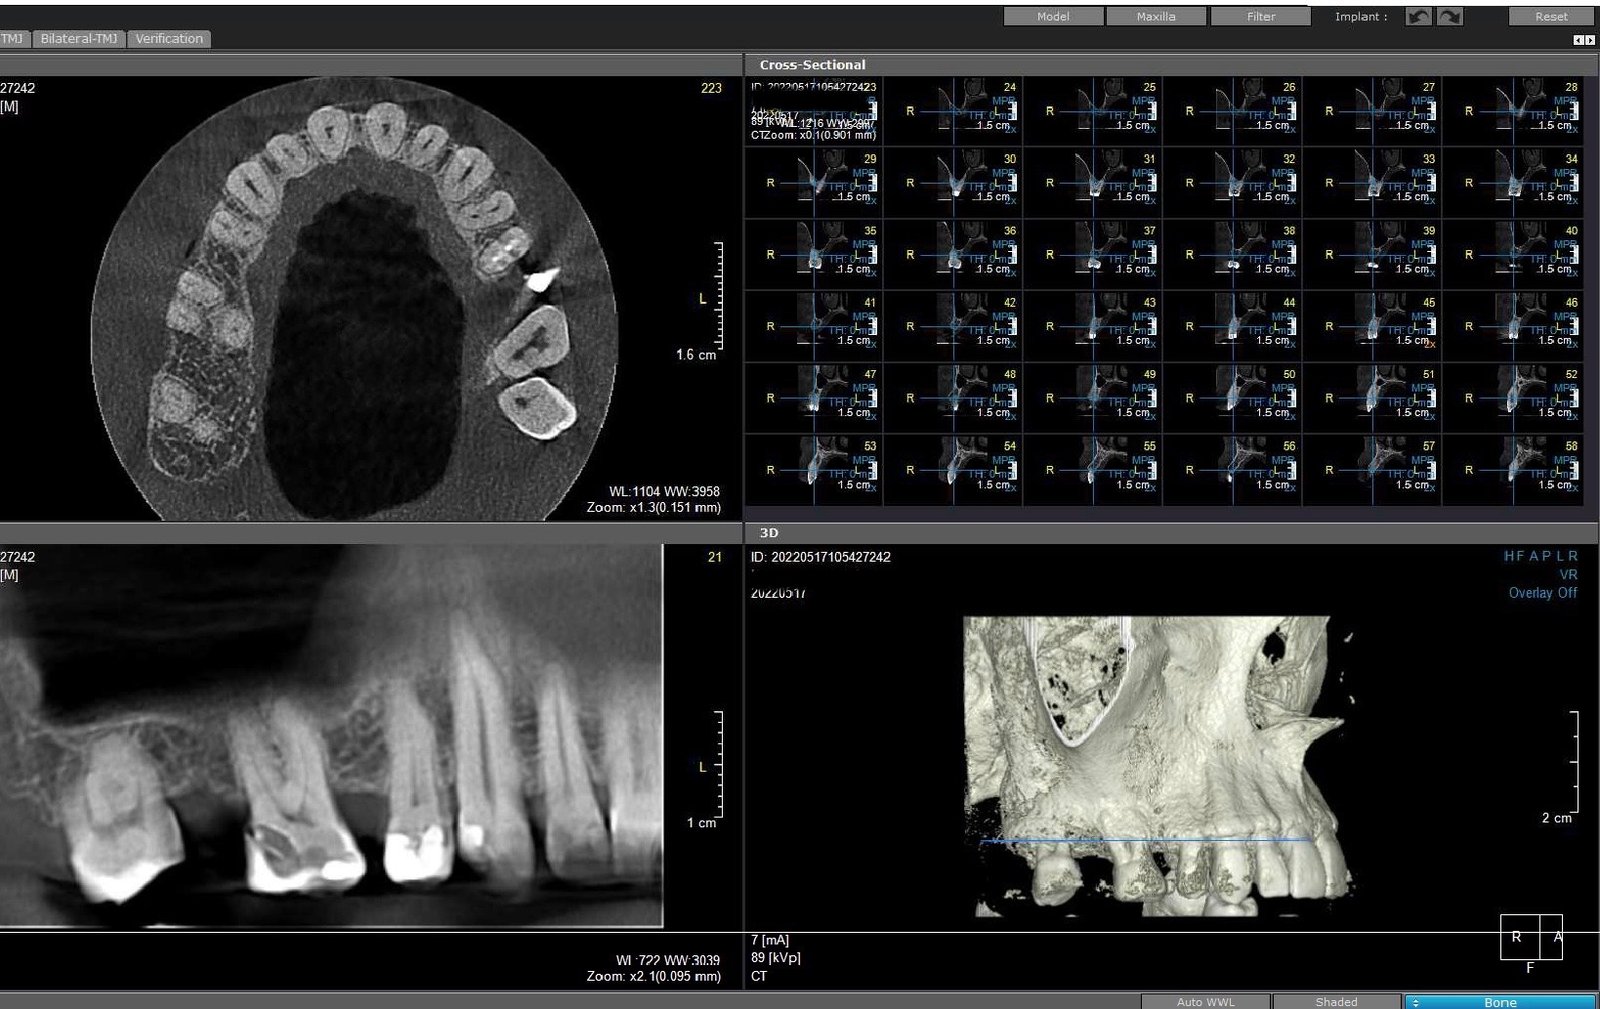

CBCT Zadar – 3D snimanje zubi

CBCT snimanje zubi u Zadru – najpreciznija 3D dijagnostika

CBCT (Cone Beam CT) je najprecizniji oblik dentalnog snimanja koji omogućuje trodimenzionalni prikaz zuba, kosti i okolnih struktura.

U Apex Dental centru u Zadru koristimo najnoviju digitalnu CBCT tehnologiju s niskom dozom zračenja i iznimnom rezolucijom.

Kada se preporučuje CBCT snimanje?

• implantologija (planiranje implantata)

• oralna kirurgija (prije vađenja zubi i zaostalih zubnih korjena)

• endodoncija (puknuća korijena, skriveni kanali, obliterirani kanali, zaostali instrumenti u kanalu)

• ortodoncija (3D prikaz struktura)

• patološke promjene (ciste, tumori)

• analiza sinusa

• procjena kvalitete i gustoće kosti

Prednosti našeg CBCT-a

• precizan prikaz do 0,01 mm

• Veliko polje snimanja (do max. 20×17 cm)

• minimalna doza zračenja

• snimka gotova odmah

• ZIP paket + DICOM + viewer

• mogućnost slanja direktno stomatologu

Apex Dental je referentni centar za CBCT snimanje u Zadru — brza usluga, vrhunska kvaliteta i profesionalan nalaz.

3D snimanje zubi Zadar

3D snimanje zubi – najnaprednija dentalna dijagnostika

3D prikaz omogućuje stomatologu potpuno planiranje zahvata bez rizika i pretpostavki.

Apex Dental koristi najsuvremeniji CBCT uređaj koji daje kristalno čiste 3D presjeke svih struktura u cjelini te je moguće segmentirati regije interesa te isprintati na 3d printeru. Na taj način Vaš stomatolog može bolje upoznati Vašu anatomiju te samim time puno sigurnije izvesti operaciju ugradnje zubnih implantata što je velika prednost i za doktora i za pacijenta. 3D snimanje preduvjet je i za digitalno 3d planiranje ugradnje zubnih implantata u specijaliziranim softverima za planiranje.

Zašto 3D snimanje?

• sigurnije planiranje implantata

• točna analiza gustoće kosti

• pregled teško dostupnih kanala

• procjena stanja sinusne membrane

• analiza patoloških promjena

• segmentacija anatomskih struktura i isporuka datoteka za 3d print

• izrada kirurških vodilica za ugradnju zubnih implantata

Snimka je gotova odmah i isporučuje se u digitalnom formatu.

3d cbct

Vrhunski 3d CBCT temelj je kompjuterski vođene implantologije. Kompjuterski vođena implantologija dobitak je kako za svakog pacijenta tako i za svakog doktora dentalne medicine!

Razlika je ogromna. Ponajprije u količini informacija koje Vaš stomatolog dobija. Ortopan je dobar ako je potrebno samo okvirno procijeniti stanje zubi i okolnih struktura jer na njemu vidimo samo dvodimenzionalnu projekciju zubi,kao na primjer kada ljeti vidimo svoju sjenu od sunca na tlu, dok je cbct trodimenzionalna snimka na kojoj u posebnom pregledniku možemo prikazati i izmjeriti svaki dio zuba i koštanih struktura što je posebno važno pri planiranju implantata ili traženju korijenskih kanala prilikom endodontskog liječenja zuba